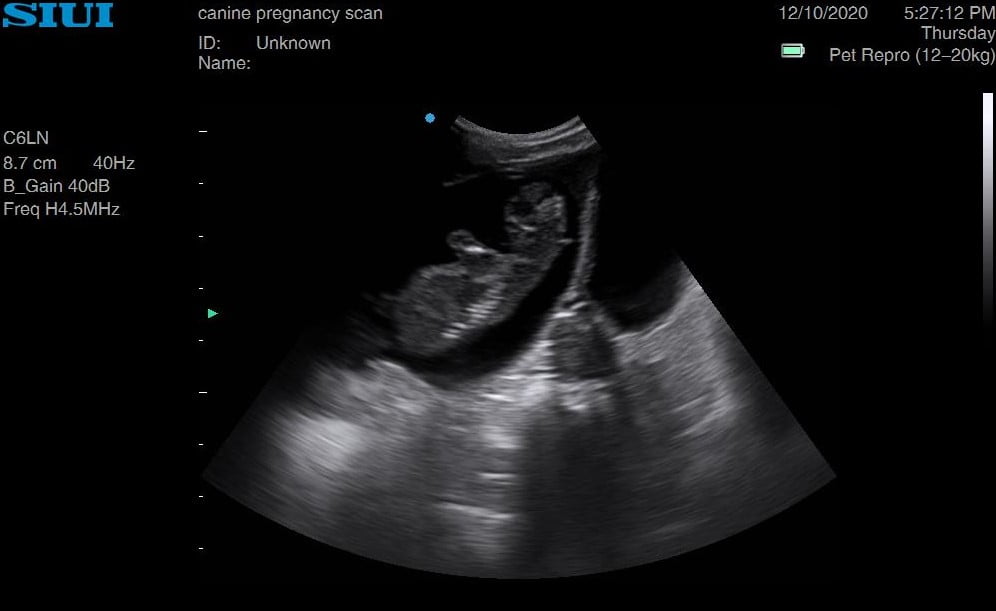

Jack Russell 6 weeks

Jack Russell already looking very rounded, head measurements at 5 weeks 6 days. She had four last litter, and we saw a minimum of four on this scan. Owners said